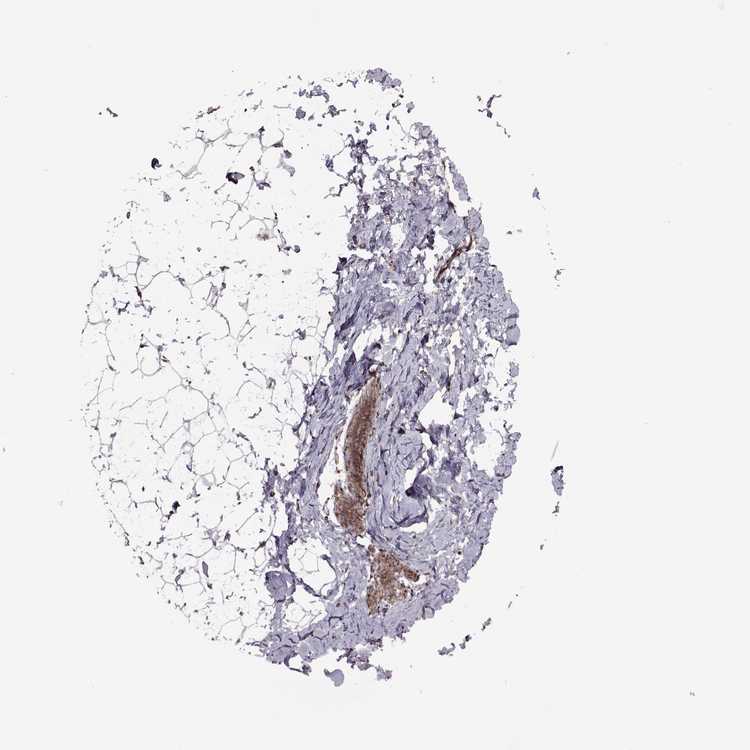

BREAST - Antibody stainingi

Antibody staining in the annotated cell types in the current human tissue is reported as not detected, low, medium, or high, based on conventional immunohistochemistry profiling in selected tissues. This score is based on the combination of the staining intensity and fraction of stained cells.

Each image is clickable and will lead to virtual microscopy that enables deeper exploration of all samples and also displays staining intensity scores, fraction scores and subcellular localization as well as patient and tissue information for each sample.

Antibody HPA075125

Adipocytes Medium

Glandular cells Medium

Myoepithelial cells Low